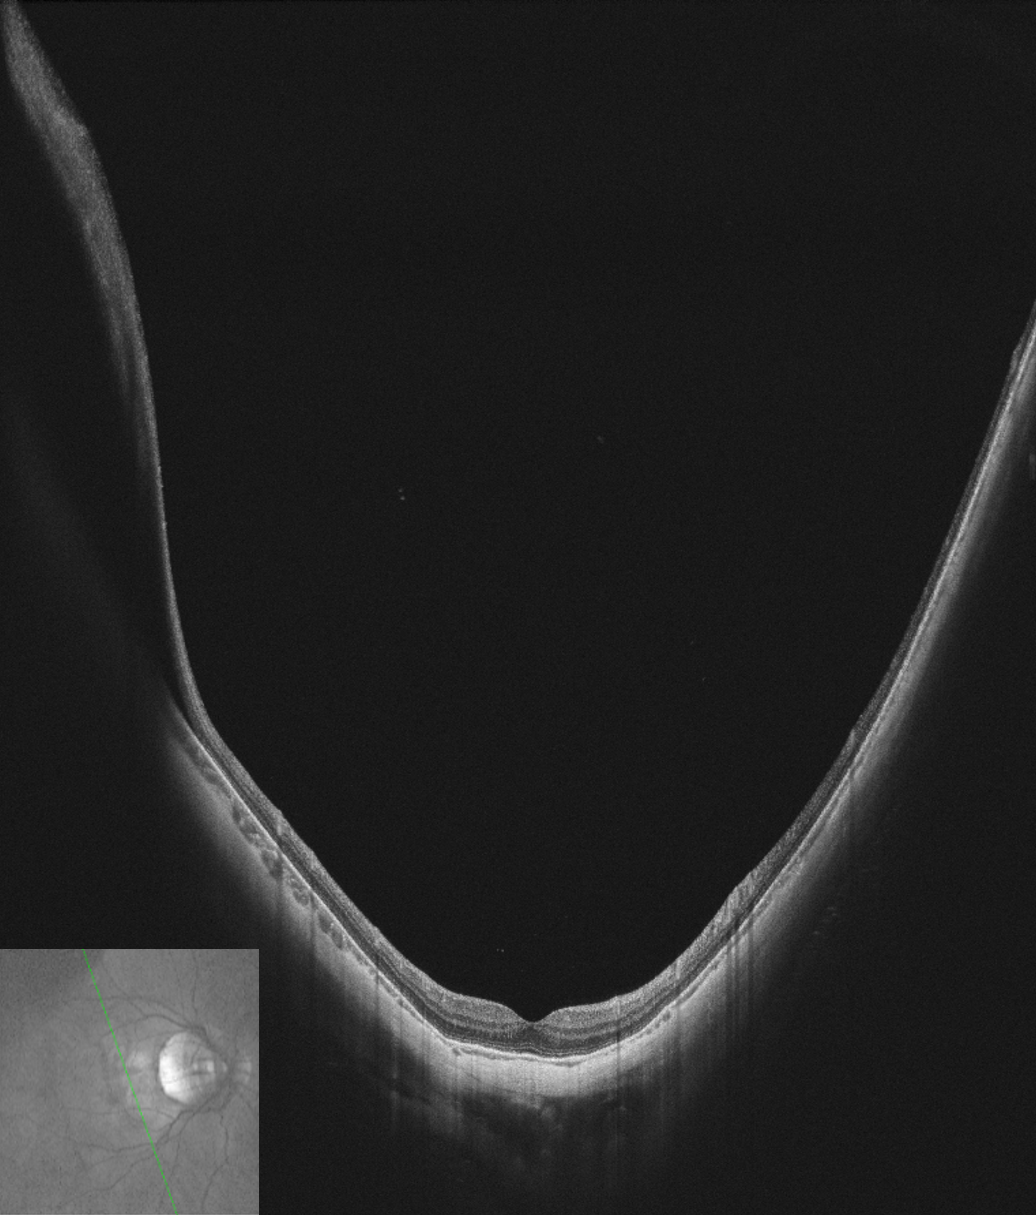

Single scan OCT image from VG-200C